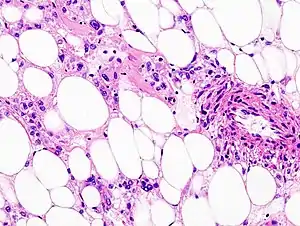

| Histopathologic image of renal angiomyolipoma. Nephrectomy specimen. H&E stain. | |

PECs consist of perivascular epithelioid cells with a clear/granular cytoplasm and central round nucleus without prominent nucleoli.

PECs typically stain for melanocytic markers (HMB-45, Melan A (Mart 1), Mitf) and myogenic markers (actin, myosin, calponin).